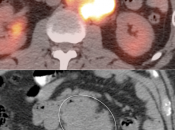

False Negatives:

• Lesions less than 8.0 mm: These very small lesions (primary or metastatic) may have minimal or no appreciable uptake, as they are “beneath the resolution of PET”.

• Poorly-Avid Primary Subtypes:

• Mucinous carcinomas

• Signet ring cell carcinoma

• Poorly differentiated adenocarcinomas

• Small FDG-avid perigastric nodes can be masked by superimposed uptake from the primary lesion.